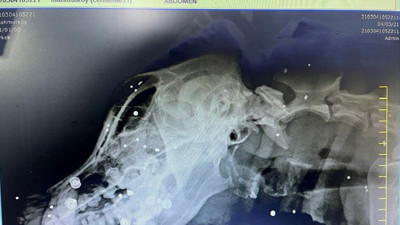

Vicdansızlık röntgen çekilince ortaya çıktı. Vücudunun her yerinde vardı Edirne'nin Keşan ilçesinde hasta olduğu sanılarak veterinere götürülen sokak köpeğinin çekilen röntgen filminde av tüfeğiyle vurulduğu ve vücudunda çok sayıda saçma olduğu belirlendi. Köpekte, vücuduna saplanan saçmalar nedeniyle kurşun zehirlenmesi ve kas erimesi saptandı.